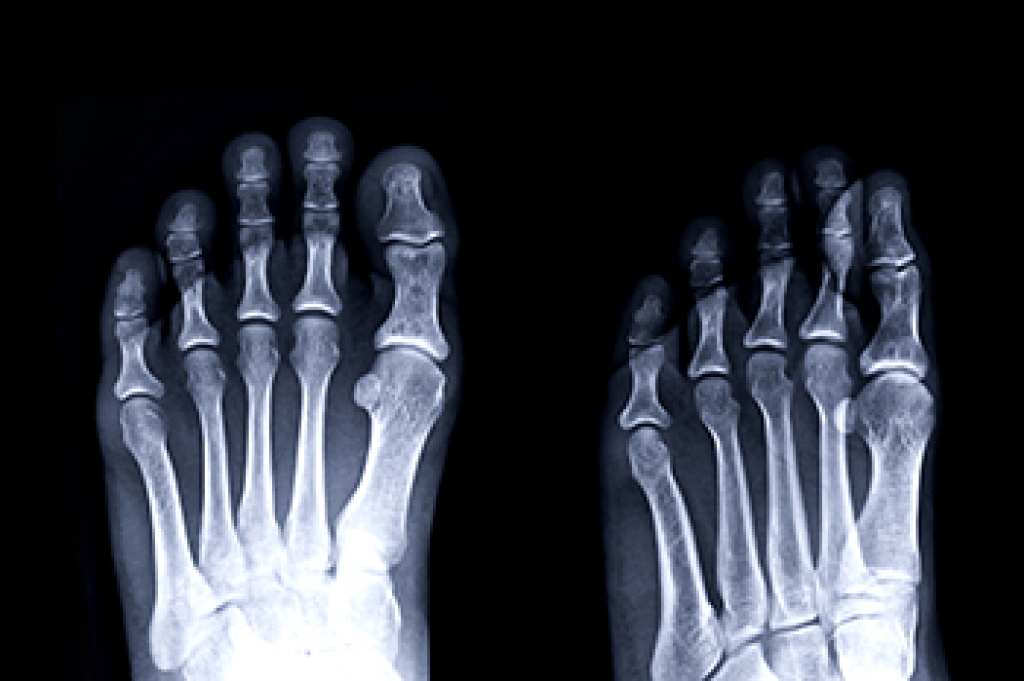

Stress fractures often occur in the feet, and can be caused by frequently participating in running and jumping activities. A stress fracture is considered to be a hairline fracture and can be uncomfortable. A patient who has a stress fracture will experience gradual pain, and many people will continue to pursue their chosen activity until walking becomes difficult. At this point, an X-ray or other imaging test can be performed to determine the severity of the stress fracture. Treatment can begin with temporarily stopping the activity and resting the foot as often as possible. Some people choose to wear a protective boot or walking cast, which can provide mobility and stability as the healing process occurs. Stress fractures can also occur from increasing speed and distance too quickly, or from wearing shoes that do not fit correctly. If you have foot pain, and think it may be from a stress fracture, it is suggested that you confer with a podiatrist who can effectively diagnose and treat this condition.